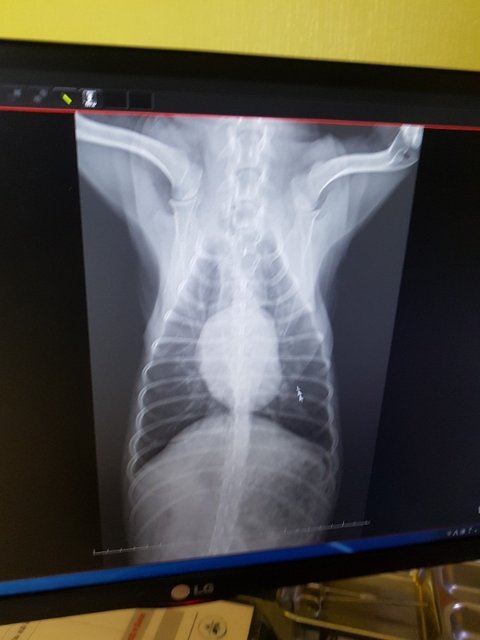

아이를 구조해 검진한결과 사상충이 아주 심각한 상태였습니다

특별한 증상이없어 전처치약을 먹는도중 갑자기 몸을 못가눌정도로 기침이 심해졌습니다

사상충때문에 오는 후유증으로 아이는 생사의 고비를 넘나들고 있습니다

입퇴원을 반복하고 있고 약이든 밥이든 먹는즉시 심한기침으로 다 토해내고 있습니다